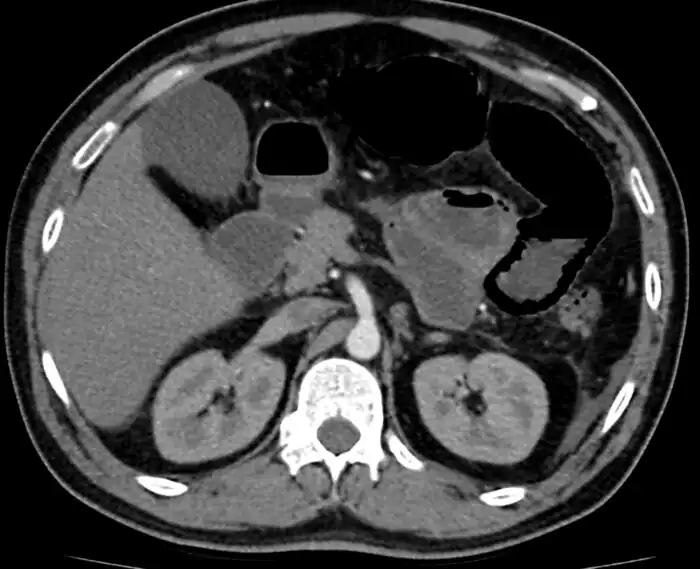

Mesenteric ischemia/CT image

Mesenteric ischemia